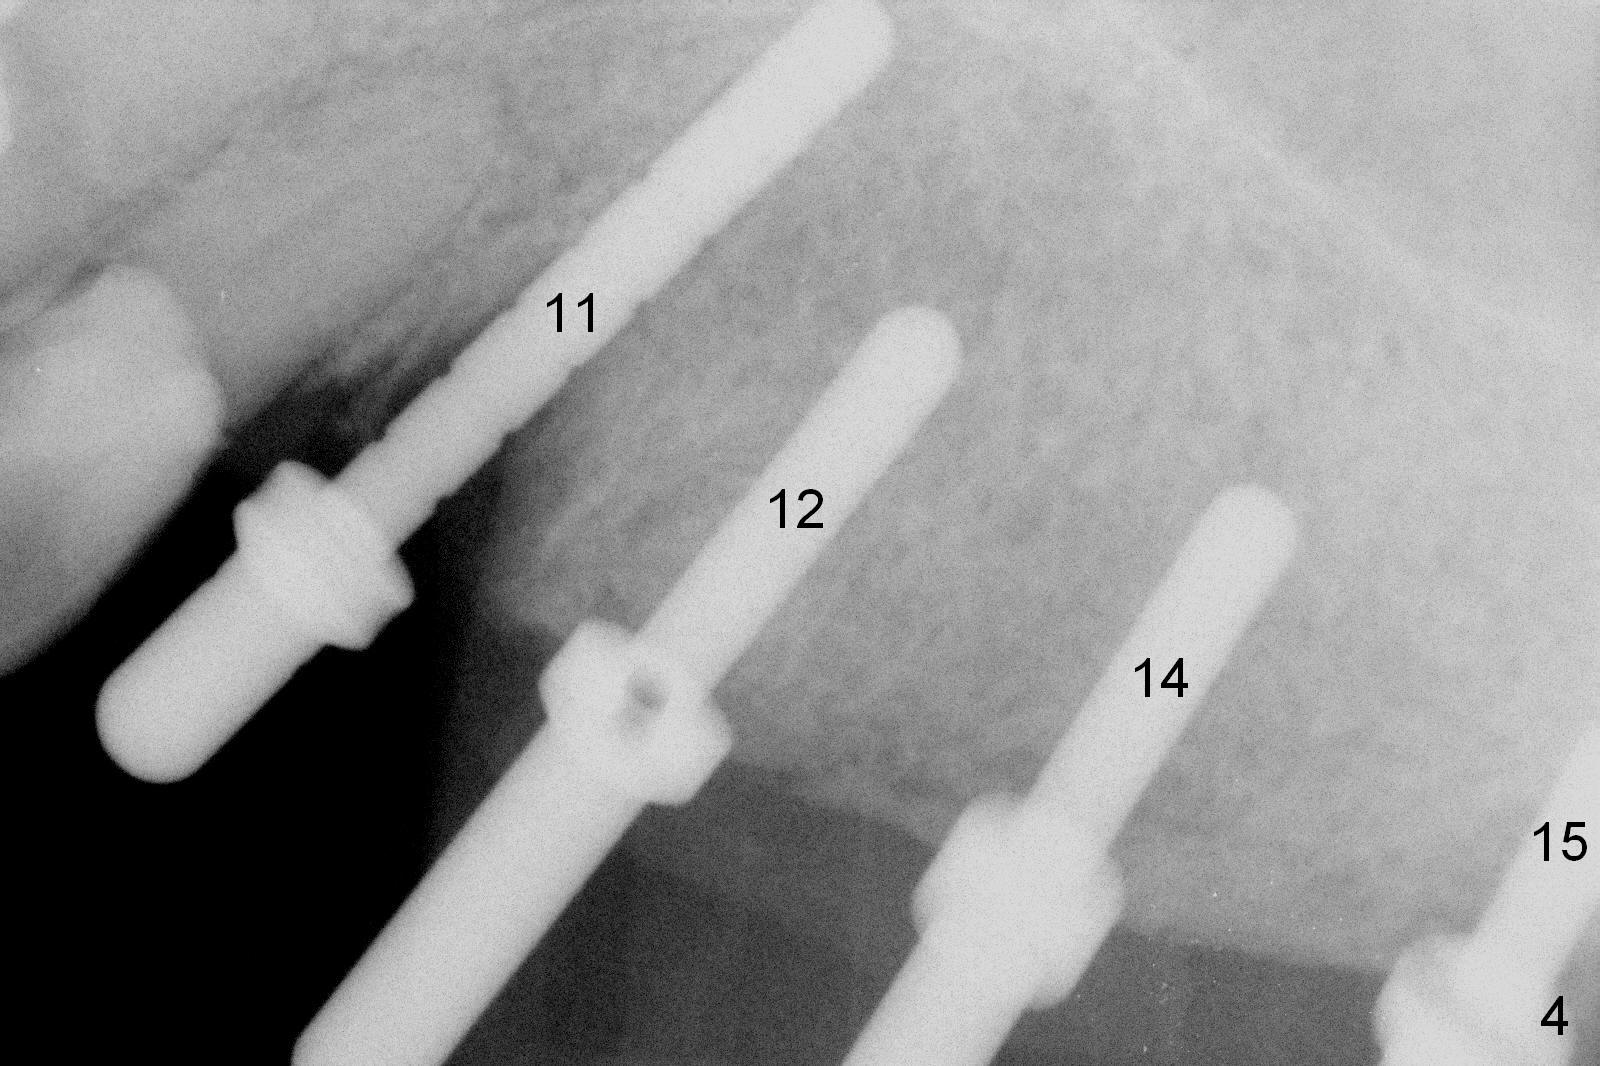

The edentulous ridge distal to #11 residual root is moderately atrophic (Fig.1). The ridge is split with 10 and 13 mm saws between initial osteotomies at #12,14 and 15 (Fig.2). Parallel pins are inserted for trajectory confirmation (Fig.3,4). The gap of the split ridge between #12 and 14 increases when bone expanders (2.7/3.6 mm) are being inserted. A 4.5x17 mm implant does not obtain primary stability at #12. When a 5x17 mm implant is being placed at #12, the buccal plate starts to crack. When the same implant is placed at #14, the crack appears to get larger. Drills are used to finish osteotomy at #14 with force being applied palatally. When the implant is re-inserted, the buccal plate fractures does not appears to get worse (Fig.5 <). In contrast, there is no obvious increase in the gap between #14 and 15 when bone expanders are being used at #15. To avoid complication, drills are used to finish osteotomy before placing a 4.5x14 mm at #15 (Fig.7 (#11: 4.5x17 mm)). CBCT shows that the bone density at #12 and 14 (400-500 Hounsfield units (HU)) is higher than that at #15 (200-300 HU). Ridge split is successful when HU is <200 with smaller diameter implants.